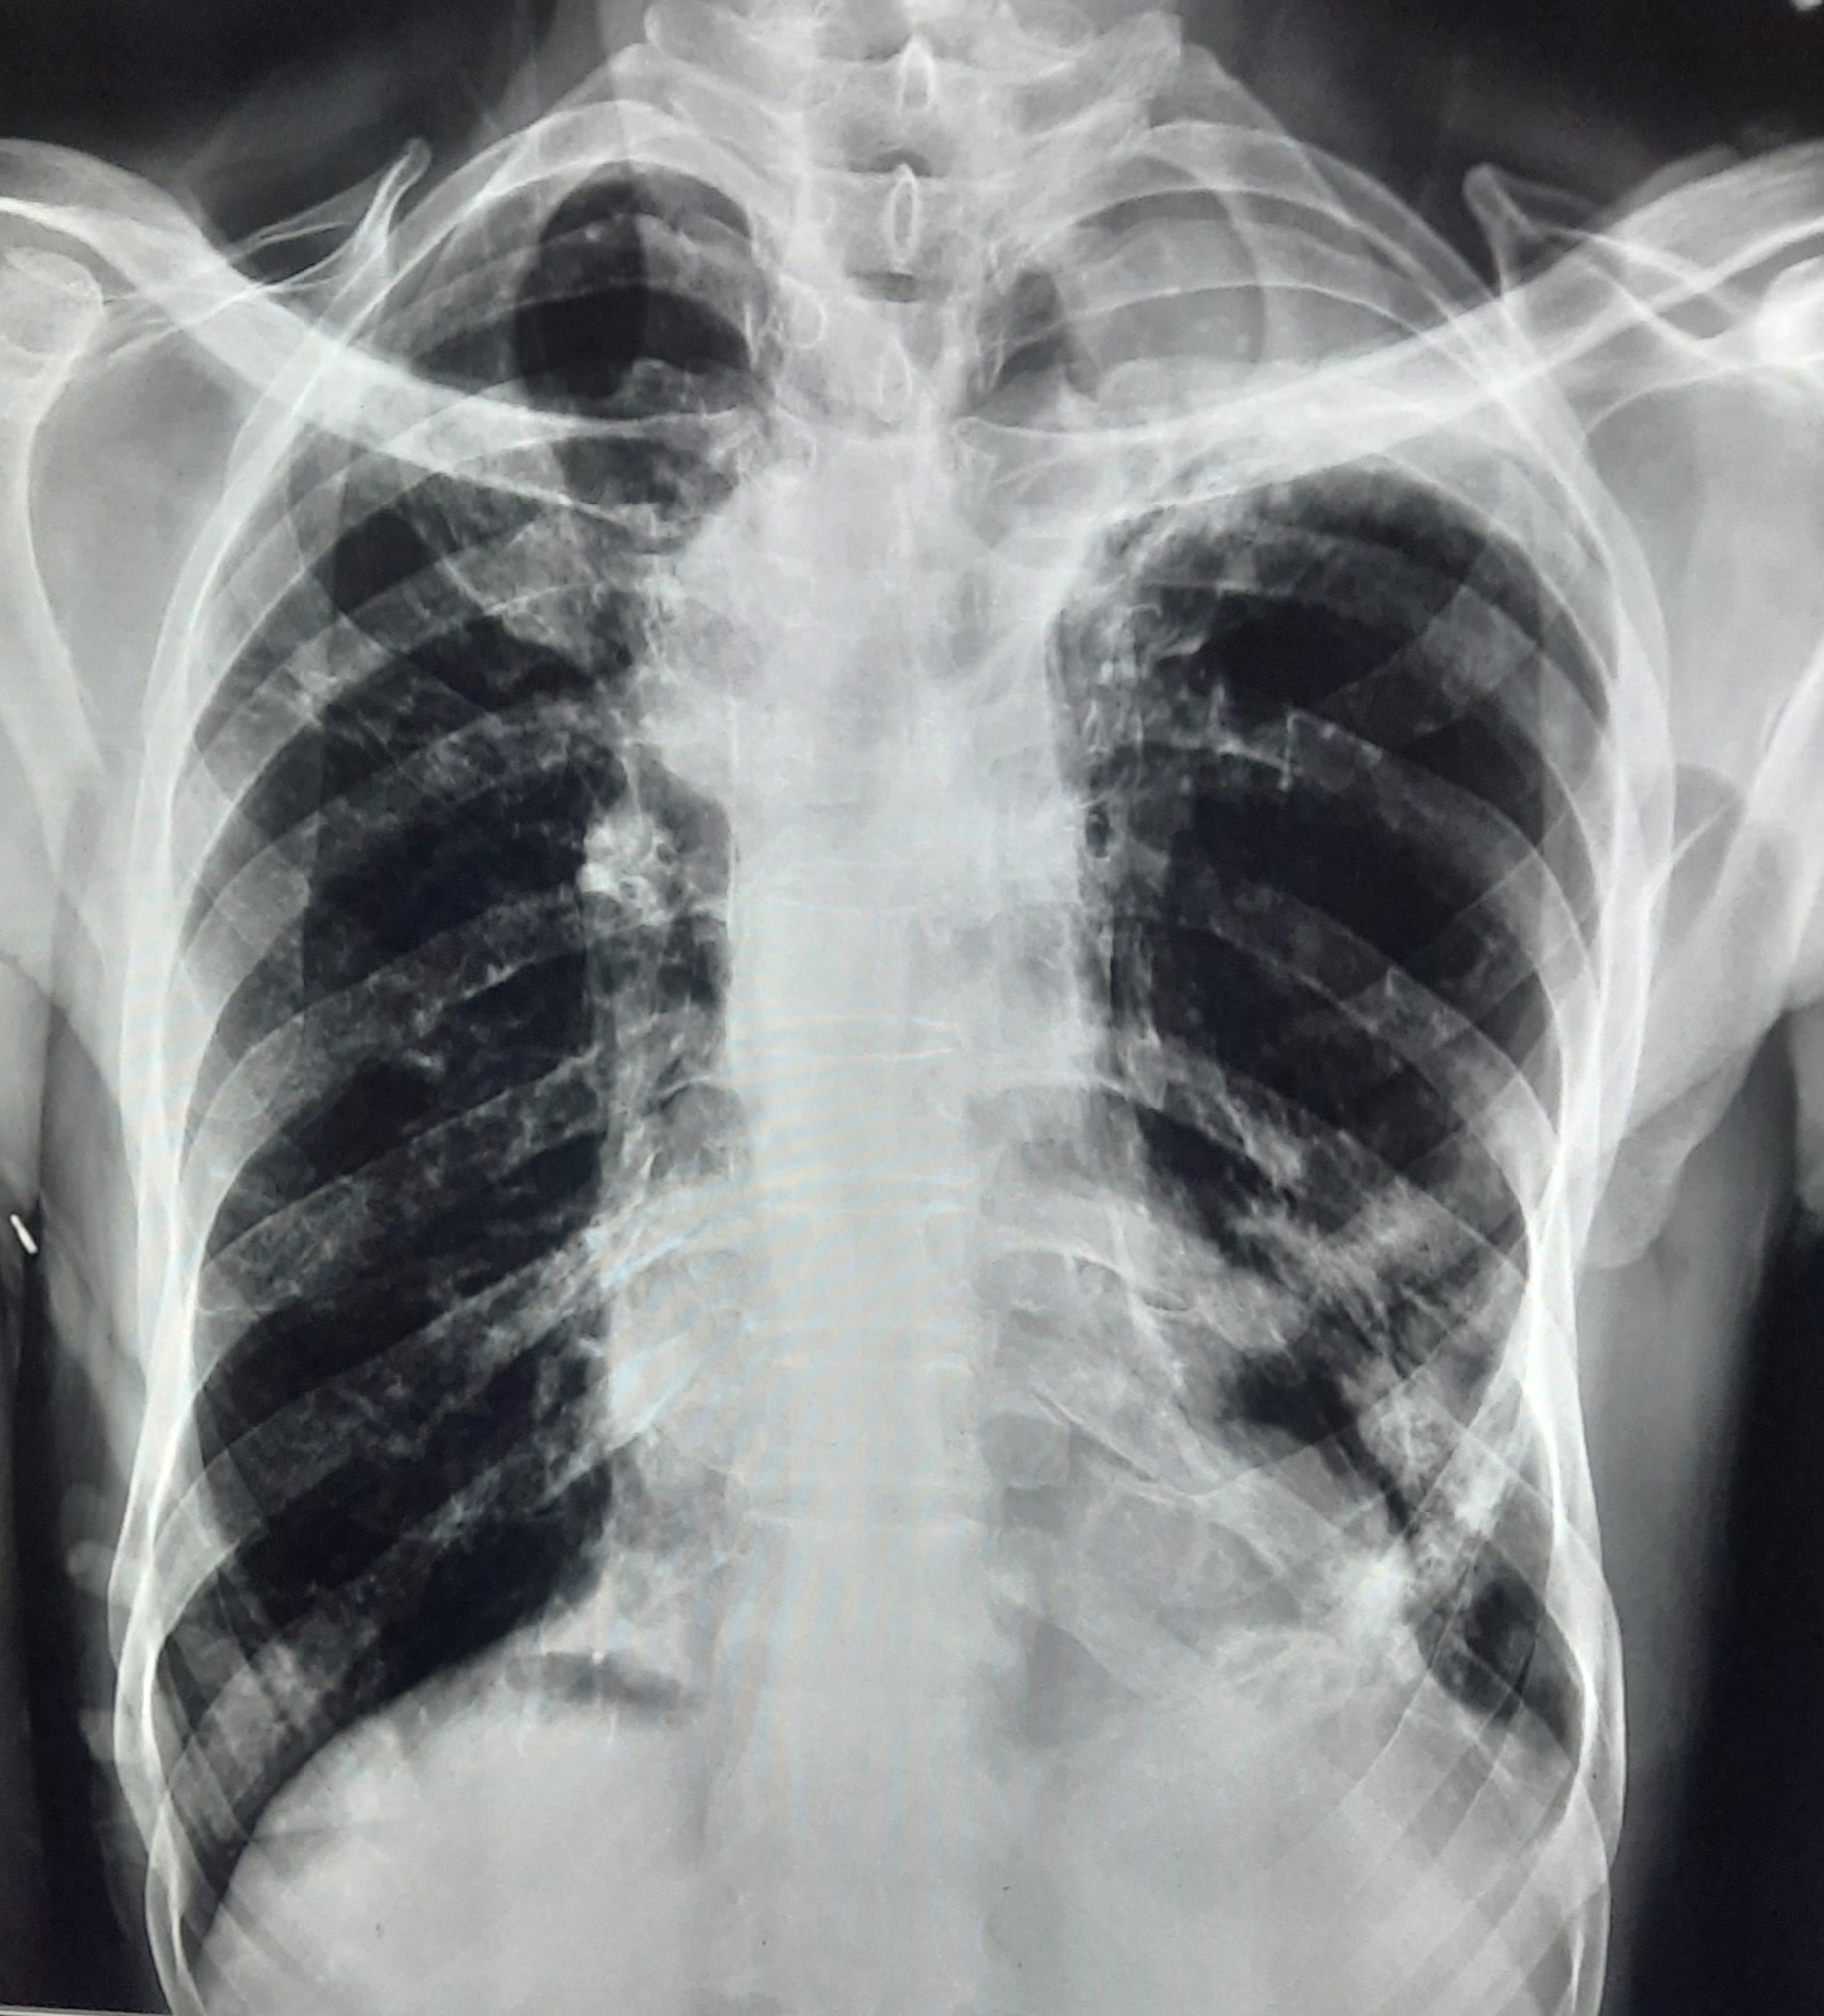

| 54 | IGGMC, Nagpur, Nagpur | P2 | 29-4418 | Pradip Bankar | Consent taken on Paper | 37 Yrs. |

Provisional Diag : Pulmonary Tuberculosis

Final Diag : Pulmonary Tuberculosis (Microbiologically Confirmed PTB) |

TB Case (Confirmed) | Left upper Zone Fibro cavitary lesion Present, Bilateral Lung Infiltration present | Abnormality visible on x-ray |